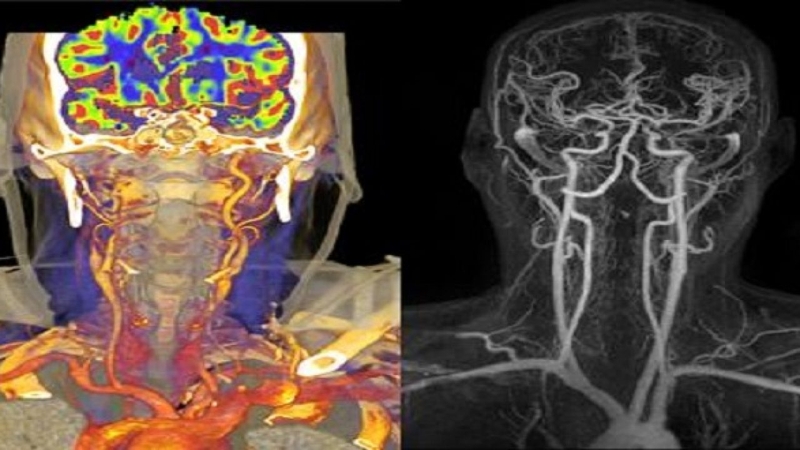

Chụp CT và MRI khác nhau như thế nào? 3 Chụp CT và MRI đều có những ưu điểm riêng trong quá trình chẩn đoán bệnh

Tùy vào tình trạng và bệnh lý của bệnh nhân mà bác sĩ có thể áp dụng các phương pháp phù hợp. Chụp CT và MRI đều có ưu điểm và nhược điểm, có thể rút ra một số khác biệt của hai phương pháp này như sau: